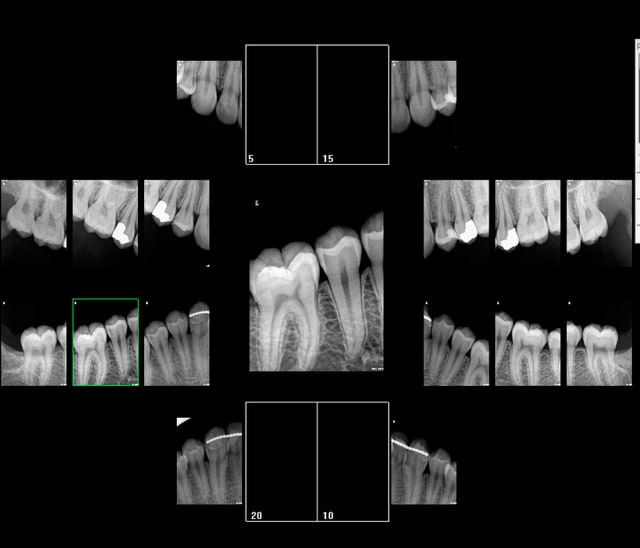

Rétro coronaires 4 secteurs dans les clous HAS et dans les clous CCAM. -)

Ca montre les couronnes et les rebords alvéolaires des secteurs concernés......... quelque soit le nombre de clichés. -)

31,92 euros et on s'évite la justification potentiellement fastidieuse d'une consult. -)

J'aurais pu compter 14 secteurs en faisant des rétro alvéolaires complètes pour cause d'antécédent de soins intensifs ( TT ortho) mais j'ai déjà allumé la lumière rouge une fois et se justifier prend pas mal de temps et je n'ai pas envie de faire un match retour. -)